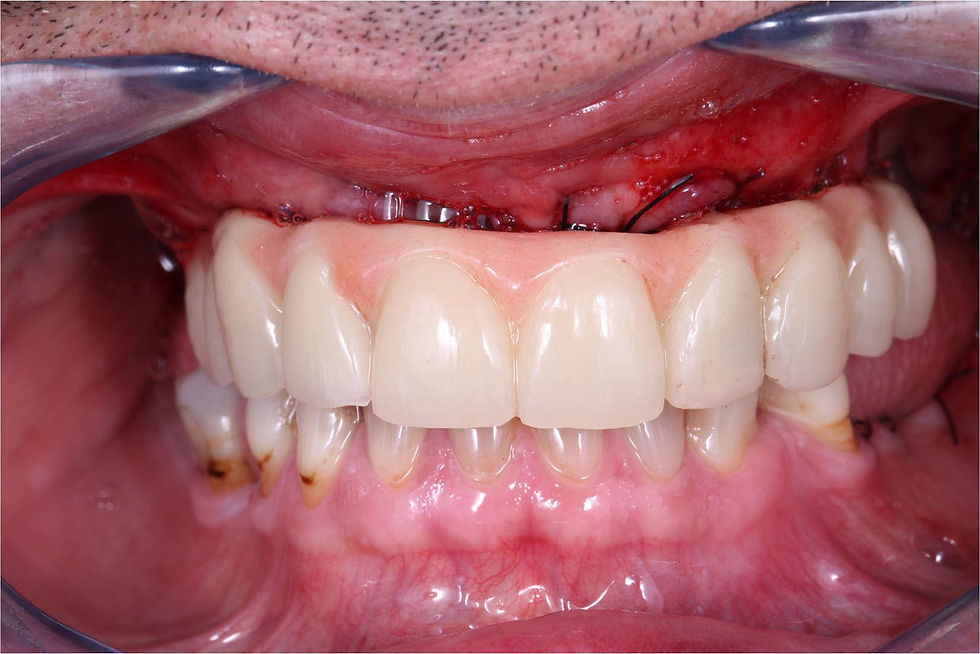

Large healing screws are inserted onto the implants and flaps are sutured. GO TO THE VIDEO

After an hour from surgery, the abutments are screwed as indicated by the dental technician and the temporary prosthesis is screwed into the patient’s mouth making the minimum necessary occlusal adjustments.